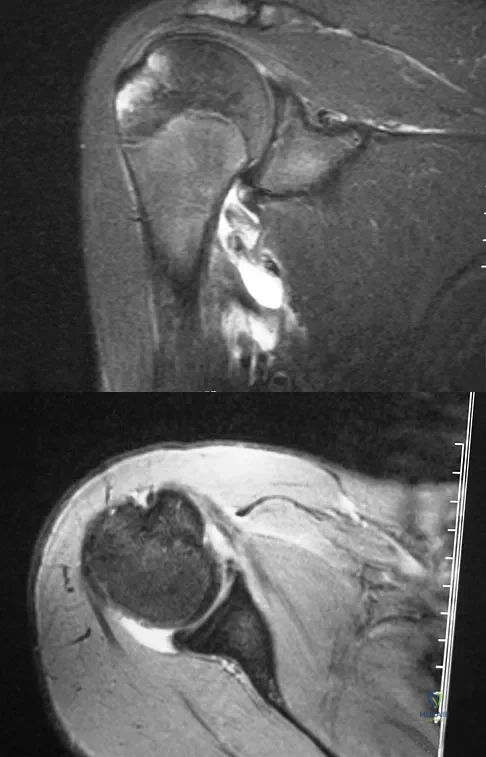

Question 78

A 15-year-old wrestler sustains an abduction, hyperextension, and external rotation injury to his right shoulder. The MRI scan findings shown in Figures 27a and 27b are most consistent with

Explanation